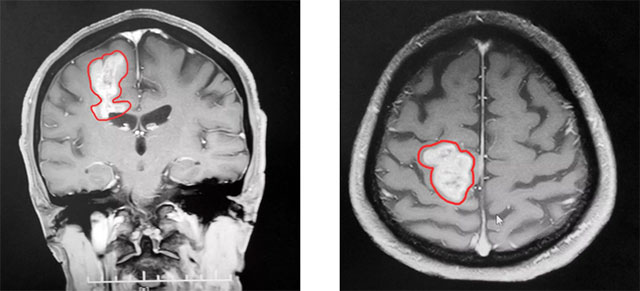

到院时,患者左下肢肌力明显下降,走路不稳。头颅MRI平扫+增强+MRS+MRSI提示:右侧顶叶占位性病变。根据患者影像学检查及检验结果分析,专家认为颅内肿瘤恶性可能性大,并肿瘤性质不明,造成患者生活质量下降,应尽快行手术治疗,明确病理诊断。

▲ MR显示肿瘤近4厘米大小

由于肿瘤位于患者右侧中央功能区,术中可能触及功能区及重要血管,手术极易造成神经功能障碍,造成患者术后肢体瘫痪,语言功能障碍等。术中术者对肿瘤边界的辨识、显微手术技巧、术区止血、周围脑组织的保护等任何一点稍有疏忽都可能出现灾难性后果,手术难度不言而喻。

李士其教授在助手吴治群博士协助下,双极电凝沿肿瘤边界,在充分保护神经功前的前提下,历时三小时,最终2.0*3.0*3.8厘米大的肿瘤被切除。